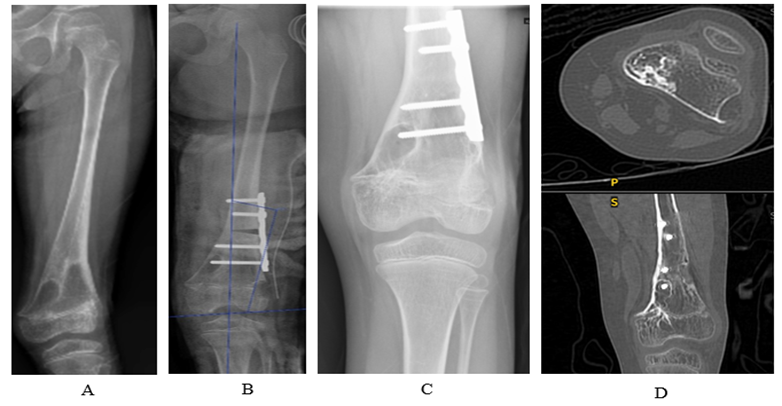

One year later, the distal physis of the left femur developed a lateral physeal bar, resulting in valgus deformity (Figure IF). A CT scan revealed the formation of a new lateral physeal bar (Figure IG). Therefore, at age of six, a second surgery involving lateral physeal bar resection and varus corrective osteotomy were performed to correct the valgus deformity (Figure II A & IIB).

Within a year, her distal left femur developed varus angulation again, attributed to the recurrence of the medial physeal bar (Figure IIC). A CT scan showed the medial physeal bar recurred with proximal migration of the bone wax (Figure IID).

Figure II: A: valgus deformity. B: early radiograph after lateral physeal bar resection and corrective osteotomy. C: successful lateral bar resection with no recurrent of valgus deformity at one year, however varus angulation redevelops. D: CT image of physeal bar reformation medially.